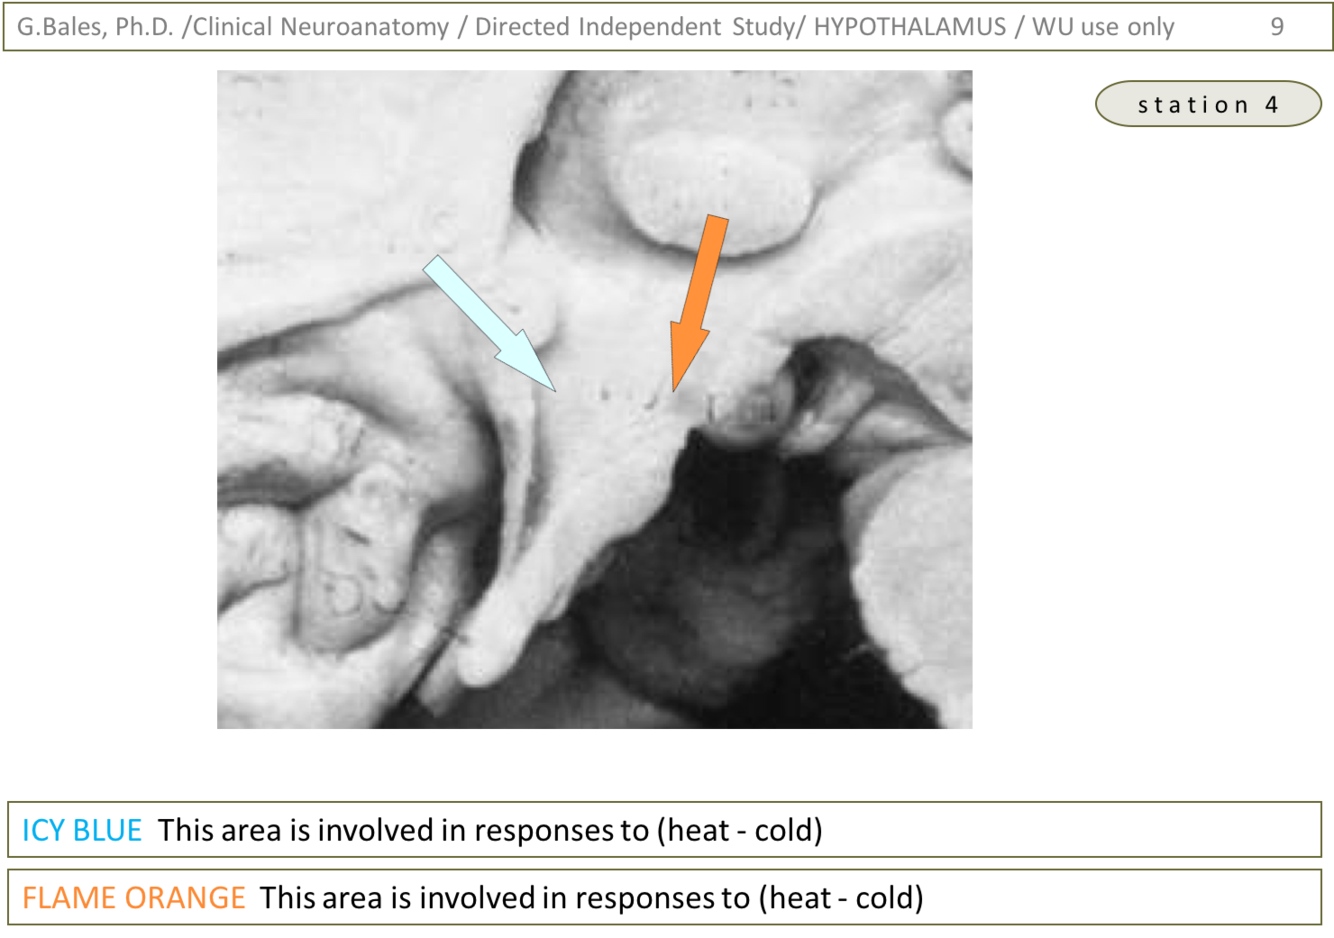

1) Icy blue – area involved in response to heat (regulates mechanisms of heat dissipation; Hypothalamus lecture – slide 30)

2) Flame orange – area involved in response to cold (heat production via vasoconstriction and shivering; Hypothalamus lecture – slide 31)